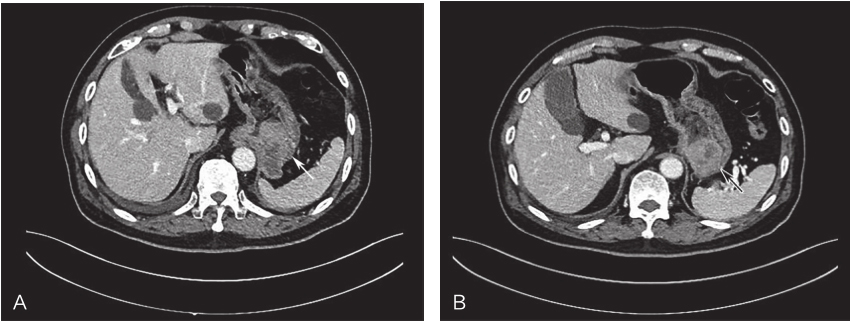

-腹部增强CT:胃贲门部及胃体分别可见两处大小分别为5cm和3cm左右、混杂密度肿块影,两处肿块增强扫描均呈现不均匀强化,考虑GIST可能(图1)。

图1术前腹部CT示胃部肿瘤

A.胃底贲门部;B.胃体部